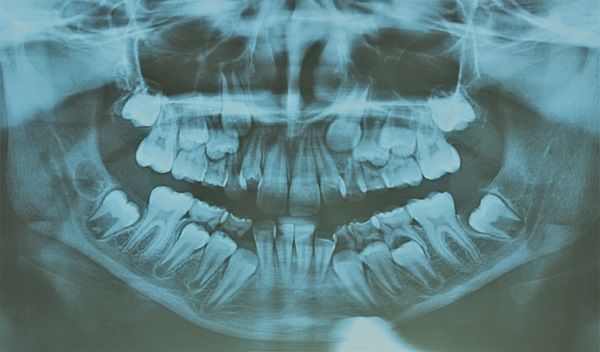

Un’ortopanoramica è un esame accurato che viene effettuato al fine di stabilire lo stato di salute dell’intero apparato dentale. Attraverso questa tecnica radiografica è possibile avere una visione d’insieme di tutto il complesso del cavo orale che include le arcate dei denti (inferiore e superiore) le ossa mandibolari e mascellari, dei seni mascellari e di ogni singolo dente.

Prima di stabilire il tipo di trattamento da applicare per una specifica patologia è essenziale prendere visione dello stato effettivo dei denti e per questo l’odontoiatra prescrive un’ortopanoramica.

I problemi dentali possono essere di diversa natura, cominciando da una carie per finire a un problema gengivale (paradontite). Altre volte la patologia può essere più complessa come danni ai tessuti interni del dente (lesioni endodontiche, tipo granulomi apicali), o persino lesioni alle ossa mascellari. In tutti questi casi siamo in grado di fare una diagnosi grazie a una serie di esami approfonditi come l’ortopanoramica ai denti che ci darà un quadro chiaro e completo della situazione.